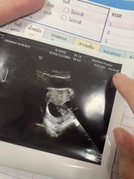

5weekจะเจอน้องไหมคะ

ไปฝากครรภ์5weekจะเห็นน้องไหมคะ ได้ยินเสียงหัวใจกี่weekค่ะ

บ้านนี้ 6 week เจอน้อง ส่วนเสียงหัวใจ 9 week 6 day ค้า

ท้องยังอ่อนอยู่ค่ะ บ้านนี่เห็นน้อง6week 5day 🥰

บ้านนี้เจอตัว กับเสียงหัวใจตอน 6weekค่ะ

เจอตอน6วีคค่ะ ผ่านช่องคลอด

บ้านนี้เห็นน้องตอน6wค่ะ